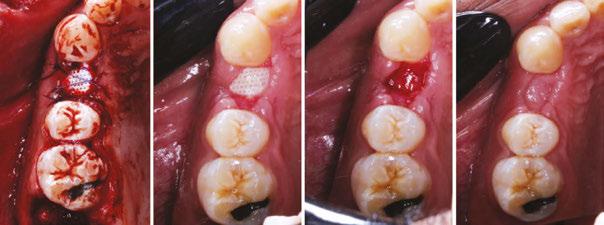

Finally, let’s revisit the opening scenario: how did I end up choosing to manage the greenstick-fractured ANS? My training certainly came in handy that day. This stressful event is evidenced by the fact that I barely managed two clinical photos that day. The patient was planned for a maxillary implant-fixed complete denture. She had an atrophic maxilla with anteriorly and inferiorly pneumatized sinuses. However, with the use of a nasopalatine implant19-20 anteriorly, I was able to achieve adequate AP spread. It was the fifth and last implant I had planned for this case. I fully prepped the osteotomy as the atrophic anterior maxilla lacks sufficient elasticity from trabecular bone. As I placed the implant and was finishing with my torque wrench around 40 Ncm, I felt and saw the ANS greenstick fracture. Since I am not trained on reconstruction plates to reduce bony fractures, I had to think fast. I decided to combine concepts from Urban’s “Sausage” technique as well as membrane tacking sutures from the Kamat’s “SauFRa” technique to stabilize the graft and the ANS. Essentially, this turned into an “unintentional” ridge split.

Figures 9A-9I: Management of ANS greenstick fracture via horizontal ridge augmentation. 9A. Pre-op. 9B: Stabilization of ANS greenstick fracture via “sausage”-based technique using two 20x30 RCMs and 4-0 PGCL sutures. Membrane-stabilizing sutures used: periosteal vertical mattress suture (PVMS) at lateral-most extent of the graft area. PVMS at the medial extent of each membrane (another PVMS was added just left of midline after photo was taken). Apical periosteal and palatal membrane tacking sutures. 2.5cc particulate 80/20 FDBA (corticocancellous)/xenograft (porcine) was used. 9C. 6-month post-op. Patient allowed limited wear of denture (shortened flange in anterior) 2 months post-op. 9D. Uncovering with view of the repaired ANS with regenerated bone. Implant placed in NP canal @ 25 Ncm. 9E. Occlusal view. 9F. L-PRF prepared (700 RCF, 8 minutes) and placed all along arch to aid in soft tissue healing. Flaps intentionally sutured to allow healing by secondary intention to increase KT. Conversion prosthesis loaded, patient educated about anterior cantilever. 9G. 1-week follow up. The power of L-PRF. 9H. 3-month follow up. 9I. Uncover at 3 months post placement of NP implant. 9J. CBCT Axial View. AP spread with (14.4 mm) and without (9.3 mm) NP implant